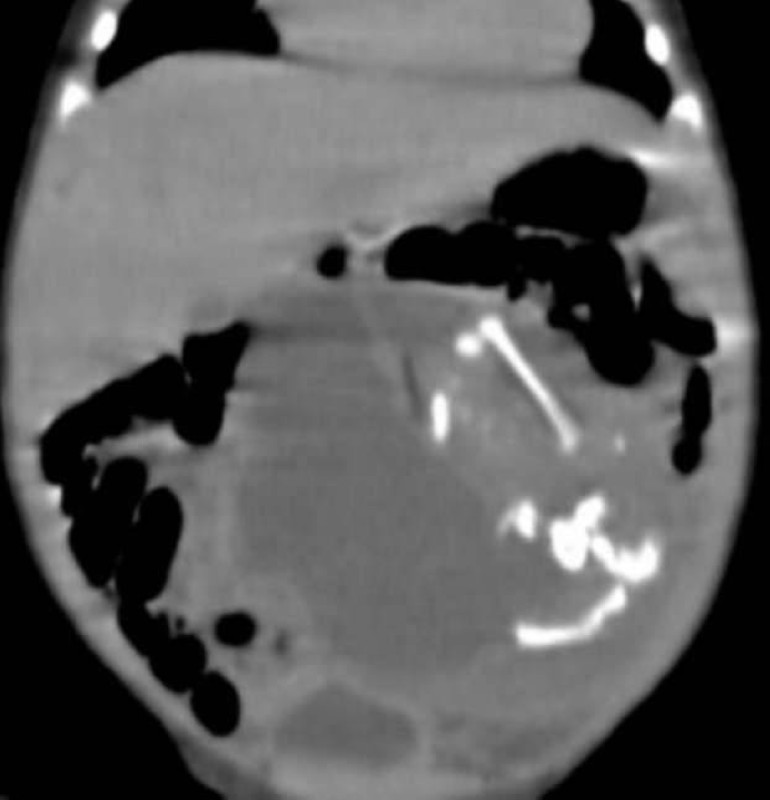

وتابع: «تمت ولادة الطفل بعملية قيصرية، ودخل الحضانة وخضع لسونار وأشعة مقطعية، وتبين وجود عظم ورأس داخل بطن المولود، واكتشفنا أنهما كانا لجنين آخر لم يكتمل، توفي في الشهر الثاني، والتصقت عظامه ورأسه بالجنين المكتمل، ودخل في بطنه».

وأشار رئيس الفريق الطبي للعملية إلى أنه على الفور بعد قضاء المولود يومين في الحضانة، بأحد المستشفيات الخاصة، تم إجراء جراحة استخراج وتنظيف لبطنه، واستخراج العظم وبقايا الرأس.